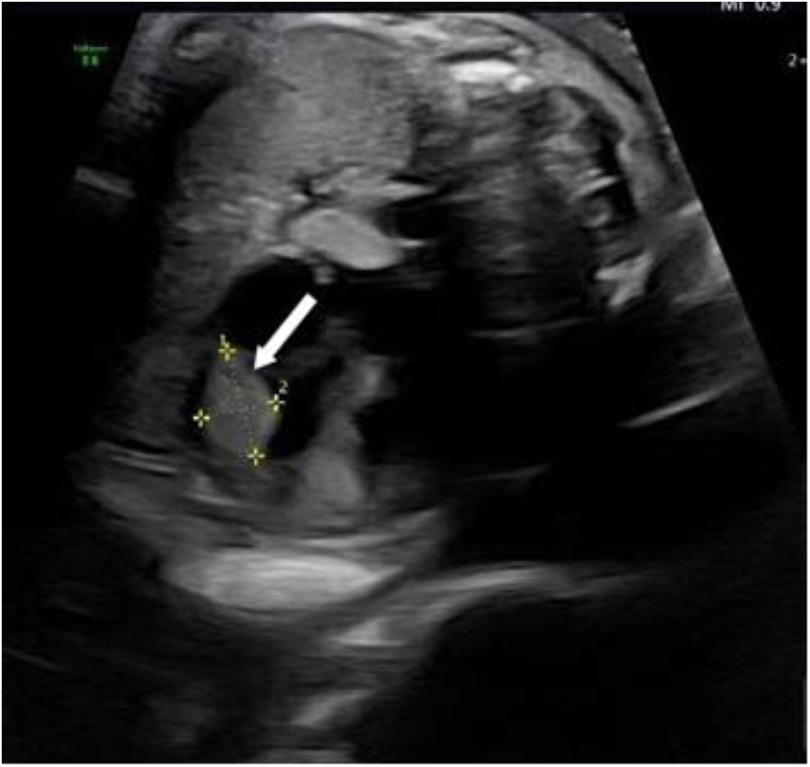

Following admission, the patient underwent further evaluations, with ultrasonography reconfirming a hyperechoic nodule near the apex of the fetal left ventricle, consistent with rhabdomyoma (Figure 1). Fetal echocardiography confirmed a 4.6 mm × 5.1 mm × 3.3 mm cardiac rhabdomyoma in the left ventricular free wall. No tricuspid or mitral valve insufficiency was detected, and cardiac output was within the normal range for gestational age. There was no evidence of fetal hydrops (ascites, pleural effusion, or skin thickening) after obtaining informed consent from the patient and her family, induction of labor was performed on March 6, 2025, via ultrasound-guided intra-amniotic injection of rivanol combined with mifepristone. Immediately following expulsion of the stillbirth, fetal skin tissue and peripheral blood samples from both parents were collected for genetic analyses, including family-based whole-exome sequencing and chromosome copy number variation (CNV) testing.

Figure 1. Ultrasonography reconfirmed rhabdomyoma near the apex of the fetal left ventricle, as as indicated by the arrow.